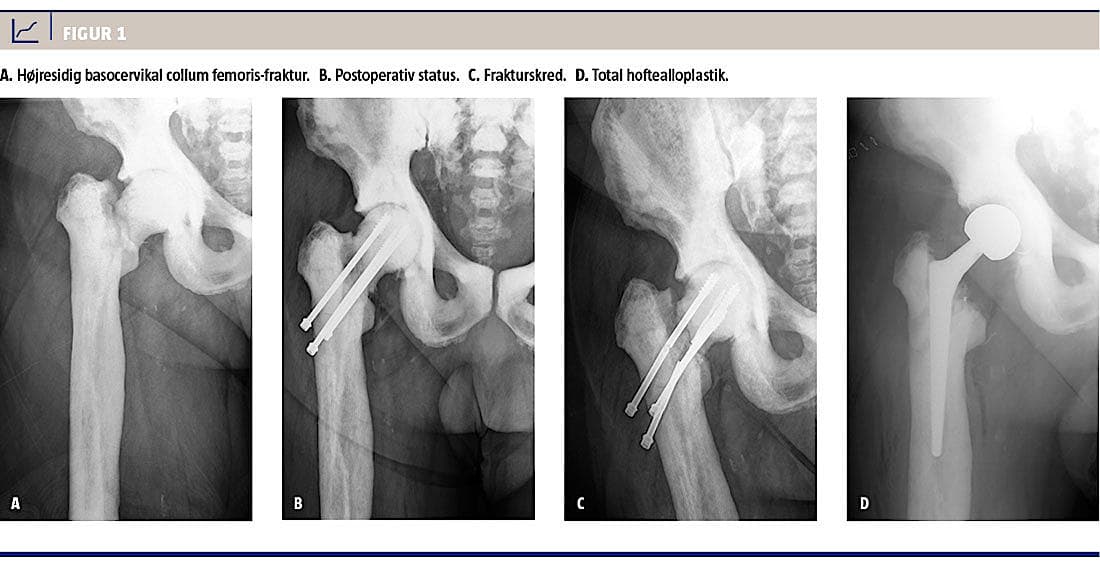

En 62-årig mand med AO og hofteartrose blev indlagt til osteosyntese med glideskrue pga. en højresidig

basocervikal collum femoris-fraktur. Ekstrem hård knoglekonsistens gjorde det imidlertid umuligt at bore gennem cortex med ledetråd, og derfor fravalgte man fiksering med glideskrue. Frakturen blev i stedet fikseret med tre kanylerede skruer. Det var dog også vanskeligt at forbore til skruer, og der blev til sidst anvendt et 6 mm-bor, som medførte suboptimal stabilitet. Et bor knækkede og måtte efterlades i collum. Det var heller ikke muligt at skære gevind, men skruerne blev fikseret i caput. Postoperative røntgenbilleder var tilfredsstillende, og patienten blev udskrevet efter et par dage.

Patienten blev langsomt mobiliseret med tiltagende belastning med klinisk og radiologisk kontrol hver 4.-6. uge. Fireogtyve uger postoperativt var der endnu ikke tegn på radiologisk heling, men der var klinisk fremgang med aftagende smerte. Det blev derfor vurderet, at frakturen var klinisk helet, og der blev påbegyndt genoptræning. Efter 52 uger havde han tiltagende smerter og nedsat gangfunktion. En røntgenoptagelse viste frakturskred og knækkede skruer (Figur 1).

Patienten blev nu tilbudt total hoftealloplastik. En CT viste en vertikal fissur forrest i acetabulum og minimal marvhule i femur. Operationen blev nøje planlagt med fremskaffelse af passende skærende værktøj. Under operationen blev der vejledt af gennemlysning og under anvendelse af highspeed-boremaskine med tungsten-carbid-bor og kuglefræser, friske bor i forskellig diametre og koniske reamere skabt plads til femurstemmet (Wagner CONE, Zimmer). Præpareringen af acetabulum var uproblematisk.